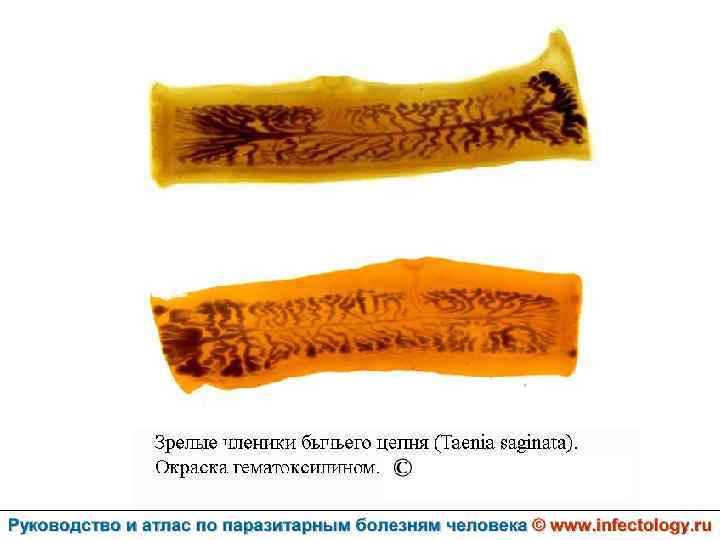

Тениаринхоз (шифр по МКБ 10 - B 68. 1) – антропонозный биогельминтоз с хроническим течением, характеризующийся преимущественно желудочно– кишечными расстройствами.